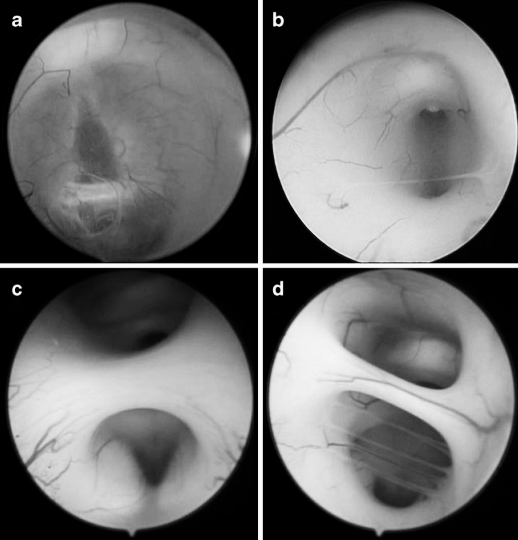

圖3 內(nèi)鏡下右側(cè)室間孔的不同形態(tài),提示第三腦室穿刺難度逐漸增大。a 水平型?b 斜向型?c 垂直型?d 垂直且孔徑縮小型

圖3 內(nèi)鏡下右側(cè)室間孔的不同形態(tài),提示第三腦室穿刺難度逐漸增大。a 水平型 b 斜向型 c 垂直型 d 垂直且孔徑縮小型